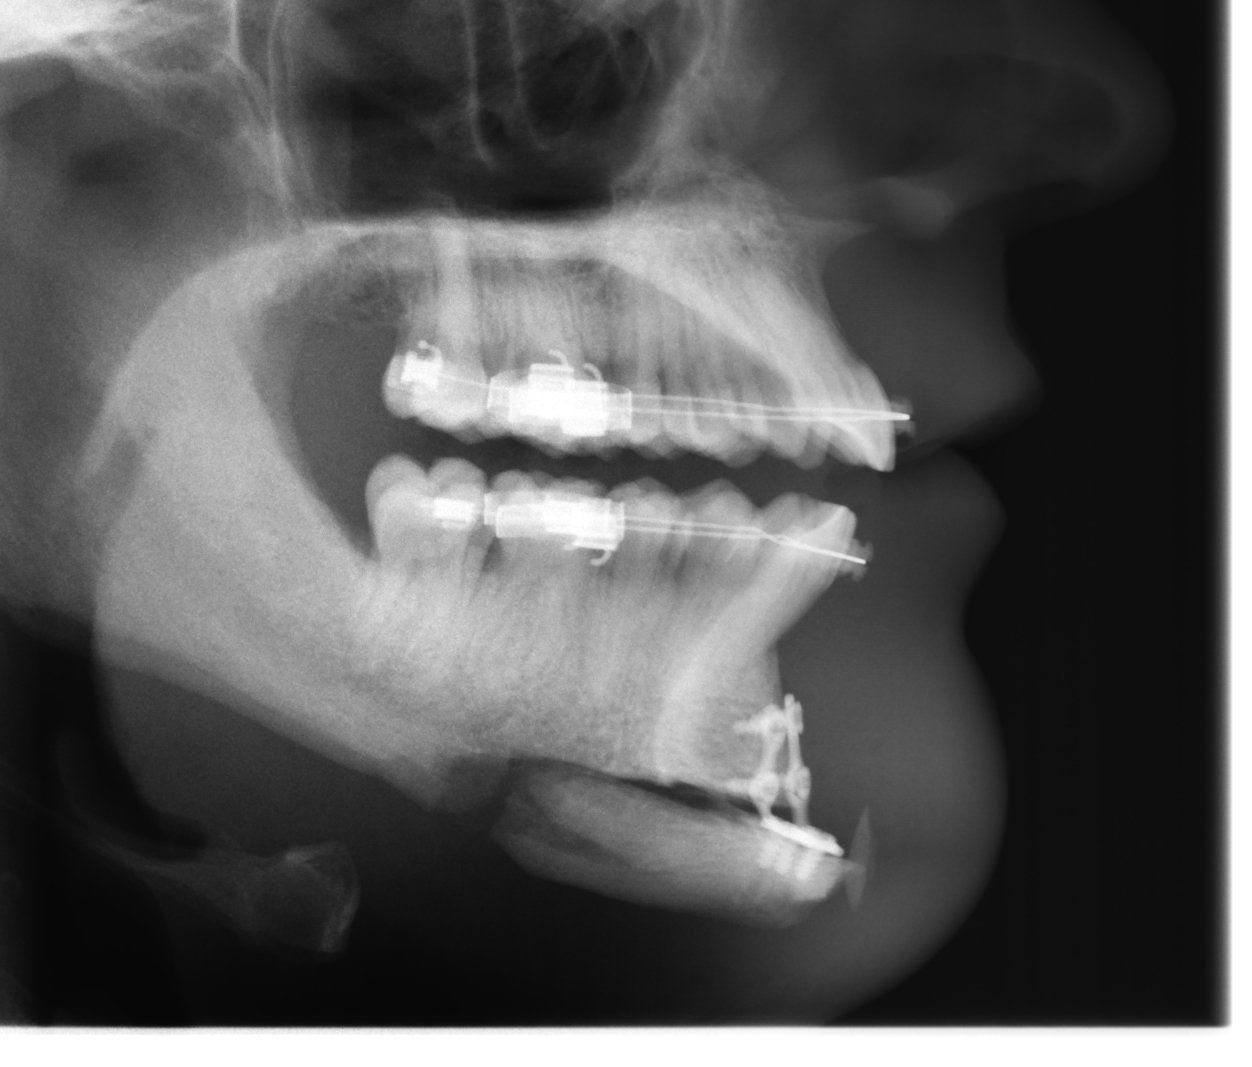

Eigenknochen kann gesägt, verschoben und entfernt werden. Kunststoff kann eingebracht und ausgetauscht werden. Der Zugang ist der Zahnfleischrandschnitt. In der Regel erfolgt die Operation in Narkose.